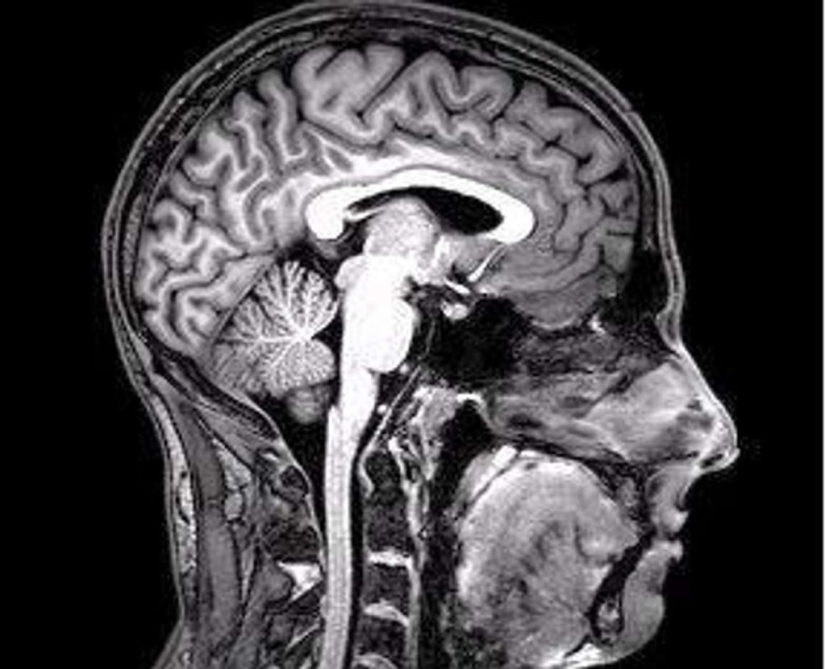

6. Aunque bostezar tradicionalmente se ha considerado un signo de somnolencia o aburrimiento, el psicólogo evolutivo Andrew Gallup dice: "Evidencia reciente sugiere que bostezar puede ayudar a enfriar el cerebro". Este efecto de "refrigeración" se produce cuando respira profundamente, estirando la mandíbula para aumentar el flujo de sangre, lo que provoca un flujo descendente de líquido cefalorraquídeo y sangre del cerebro. Esto permite que el aire entrante enfríe ligeramente los líquidos. ¿Y por qué hacemos esto de noche? Según Gallup, “Por la noche, cuando estamos a punto de irnos a la cama, la temperatura de nuestro cerebro y nuestro cuerpo alcanza su punto más alto durante el día”.